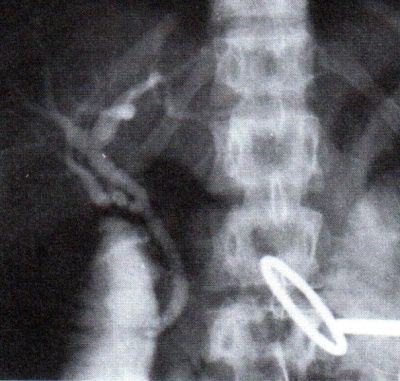

אם האבן תקועה וחוסמת, אפשר להעביר Stent מעל לאבן לניקוז המרה, ואז לתכנן את הוצאתה בתנאים טובים יותר (תצלום 35.8).

אפשר גם להשאיר צנתר נאזו-ביליארי, כלומר צנתר שקצהו האחד יושב בתוך הכולדוכוס וקצהו האחר עובר דרך מערכת העיכול ויוצא דרך האף, ודרכו לבצע שטיפות של הכולדוכוס בחומרים הממיסים אבנים.

ב- PTC לאחר שמעבירים צנתר לכולדוכוס ומזהים את האבן, מעבירים דרכו סל, לוכדים את האבן ודוחפים אותה דרך הפפילה לתריסריון, או להחדיר סטנט לדרכי המרה העוקף את האבן החוסמת.